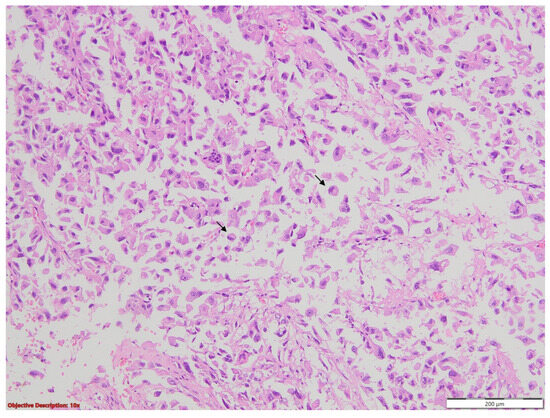

3.1. Case No. 1

3.2. Case No. 2

3.3. Case No. 3

3.4. Case No. 4